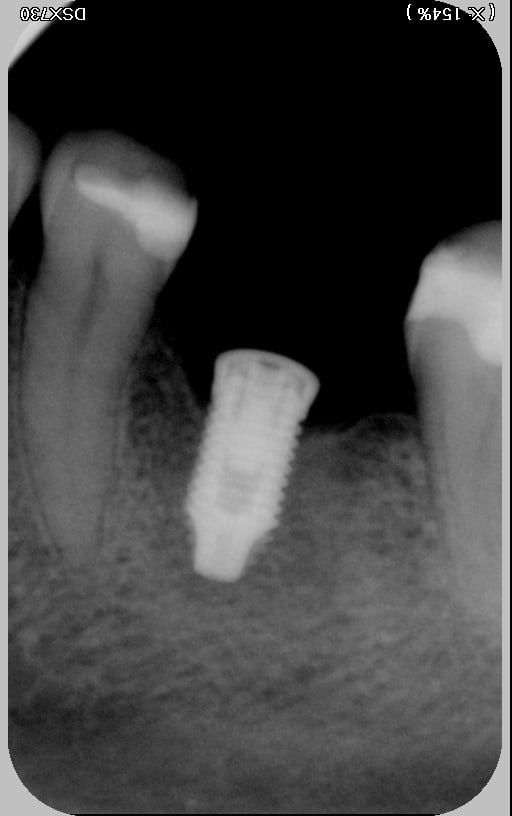

Cet implant posé en Amérique, vous dit-il quelque chose ?

Le but est de trouver un système compatible pour pouvoir le restaurer.

Nobel, connexion hexagone externe